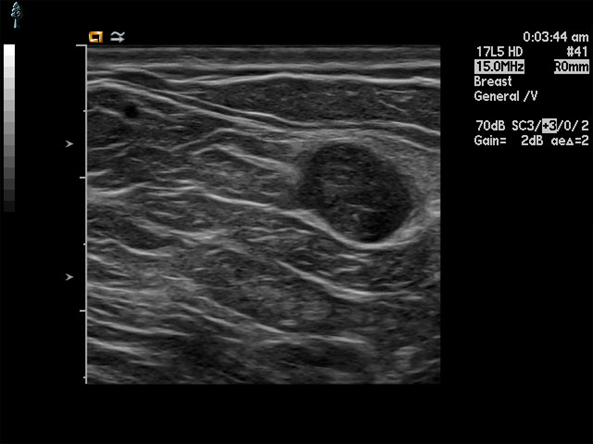

What are theses images showing?

fibroadenoma on ultrasound